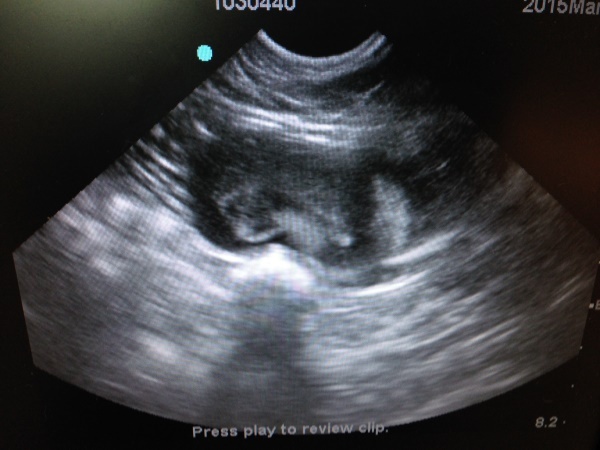

- 編號: 5725

主題: 尿路感染的志明 申請者姓名: 臺北市支持流浪貓絕育計劃協會 花色: 申請日期: 2015-03-25 16:00:25 申請者部落格: 申請者臉書網址: 所在縣市/合作醫院: 台北市/極光動物醫院 治療費用: 3690元 需求人數: 8人 已結案 (2021-06-03 00:05:00) 報名人員: yvonne(已付款)、Nancy Chai(已付款)、Sunny Chen(已付款)、道森(已付款)、Ying Tung Chen(已付款)、Tiffany Cheung x3(已付款)、 候補人員: 動物病情說明: 協會粉絲團有人通報苗栗公館一隻狀況非常糟糕的浪喵,照片看來有一條腿已截肢...該區志工立刻前往誘捕,趕到現場並未發現該貓咪蹤影,連續幾天守候終於抓到,立刻送台北協會配合醫院檢查,發現雙後腿都已經截肢,是經過醫療處理過的,卻沒有結紮被野放任他在外自生自滅,還有輕微的鼻氣管炎,在醫院大吃罐頭,抽血檢驗都很配合,雖然有點鼻氣管炎,眼睛紅腫淚眼汪汪,但還是努力在進食,很遺憾愛滋篩檢結果為陽性,免疫力較一般貓差,感冒治癒後進行結紮並洗牙拔牙治療牙齦炎,術後帶回安養之家照顧,2014/6/4至今

志明已經變得白白胖胖肥肥嫩嫩,有6.8公斤的巨大體型,雖然他的雙腳斷肢因為摩擦有厚厚的繭,在室內還是鋪了厚紙板讓志明行走更加舒服,2015/3月起照顧員發現志明排尿似乎有點困難在砂盆裡蹲很久,送醫檢查,採尿送檢,尿中有草酸鈣結晶,醫生建議要吃泌尿道處方,並給予利尿通幫助,醫療檢驗費用還請各位幫忙